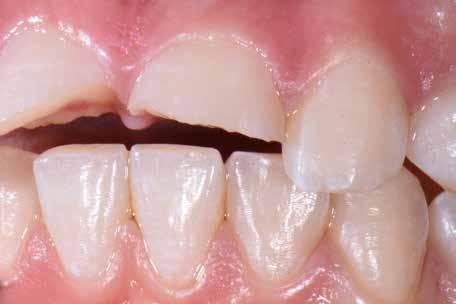

A páciens tisztában volt a felső állcsont frontrégiójában elhelyezkedő fogainak és néhány hátsó fogának kopásával. Ez az állapot a dentin jelentős mértékű expozíciójához vezetett, amely nagyfokú érzékenységet és esztétikai problémát okozott a frontrégióban, különösen mosolygáskor (1. ábra). Emellett a fogak torlódása és Angle III. osztályú moláris viszony is látható volt, amely eltérést az okklúzióban, illetve III. osztályú kismetsző anomáliára és élharapásra való hajlamot eredményezett (2. ábra).